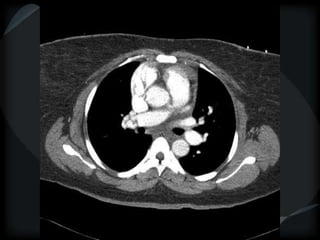

Septal Pattern – lymphatic/venous

 Secondary lobule outlined- interlobular septum

● Smooth – pulmonary veno-occlusive disease, mitral

stenosis, capillary hemangiomatosis, LC

● Beaded – lymphangitic carcinomatosis, lymphoma,

lymphangiomatosis, sarcoid

Rare = non-Langerhans’ cell histiocytosis (bone+pleura)

amyloidosis

PHTN – PA 39mm

39.2mm

PHTN and septal thickening

? PVOD